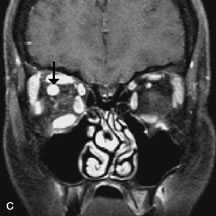

Fig. 18. A. T1-weighted, (B) T2-weighted fat-suppressed, and (C) T1-weighted fat-suppressed MR scans demonstrate a small dermoid cyst arising near the palpebral portion of the lacrinal gland (arrows). The lesion is similar in signal intensity to fat on the T1-weighted scan (A) consistent with a high adipose tissue content. The lesion shows fat-suppression and low signal intensity on the two fat-suppressed sequences (B and C) confirming its high lipid content.

Dermoid cysts appear as rounded, well-defined lesions typically contiguous with an orbital bony suture. The high-intensity signal on T1-weighted images is attributed to the sebaceous-produced lipid contents (Fig. 18).31,50 Mucoceles may demonstrate a hypointense or hyperintense signal on MR images, depending on the concentration of proteinaceous or inflammatory fluid components. The integrity of the bony walls of the expanded sinus cavities cannot be assessed on MR as well as by CT.37,50,55,56 A high-signal intensity on Tl- and T2-weighted images is characteristic of orbital chronic hematic cysts because of the blood-breakdown products within the cysts.57